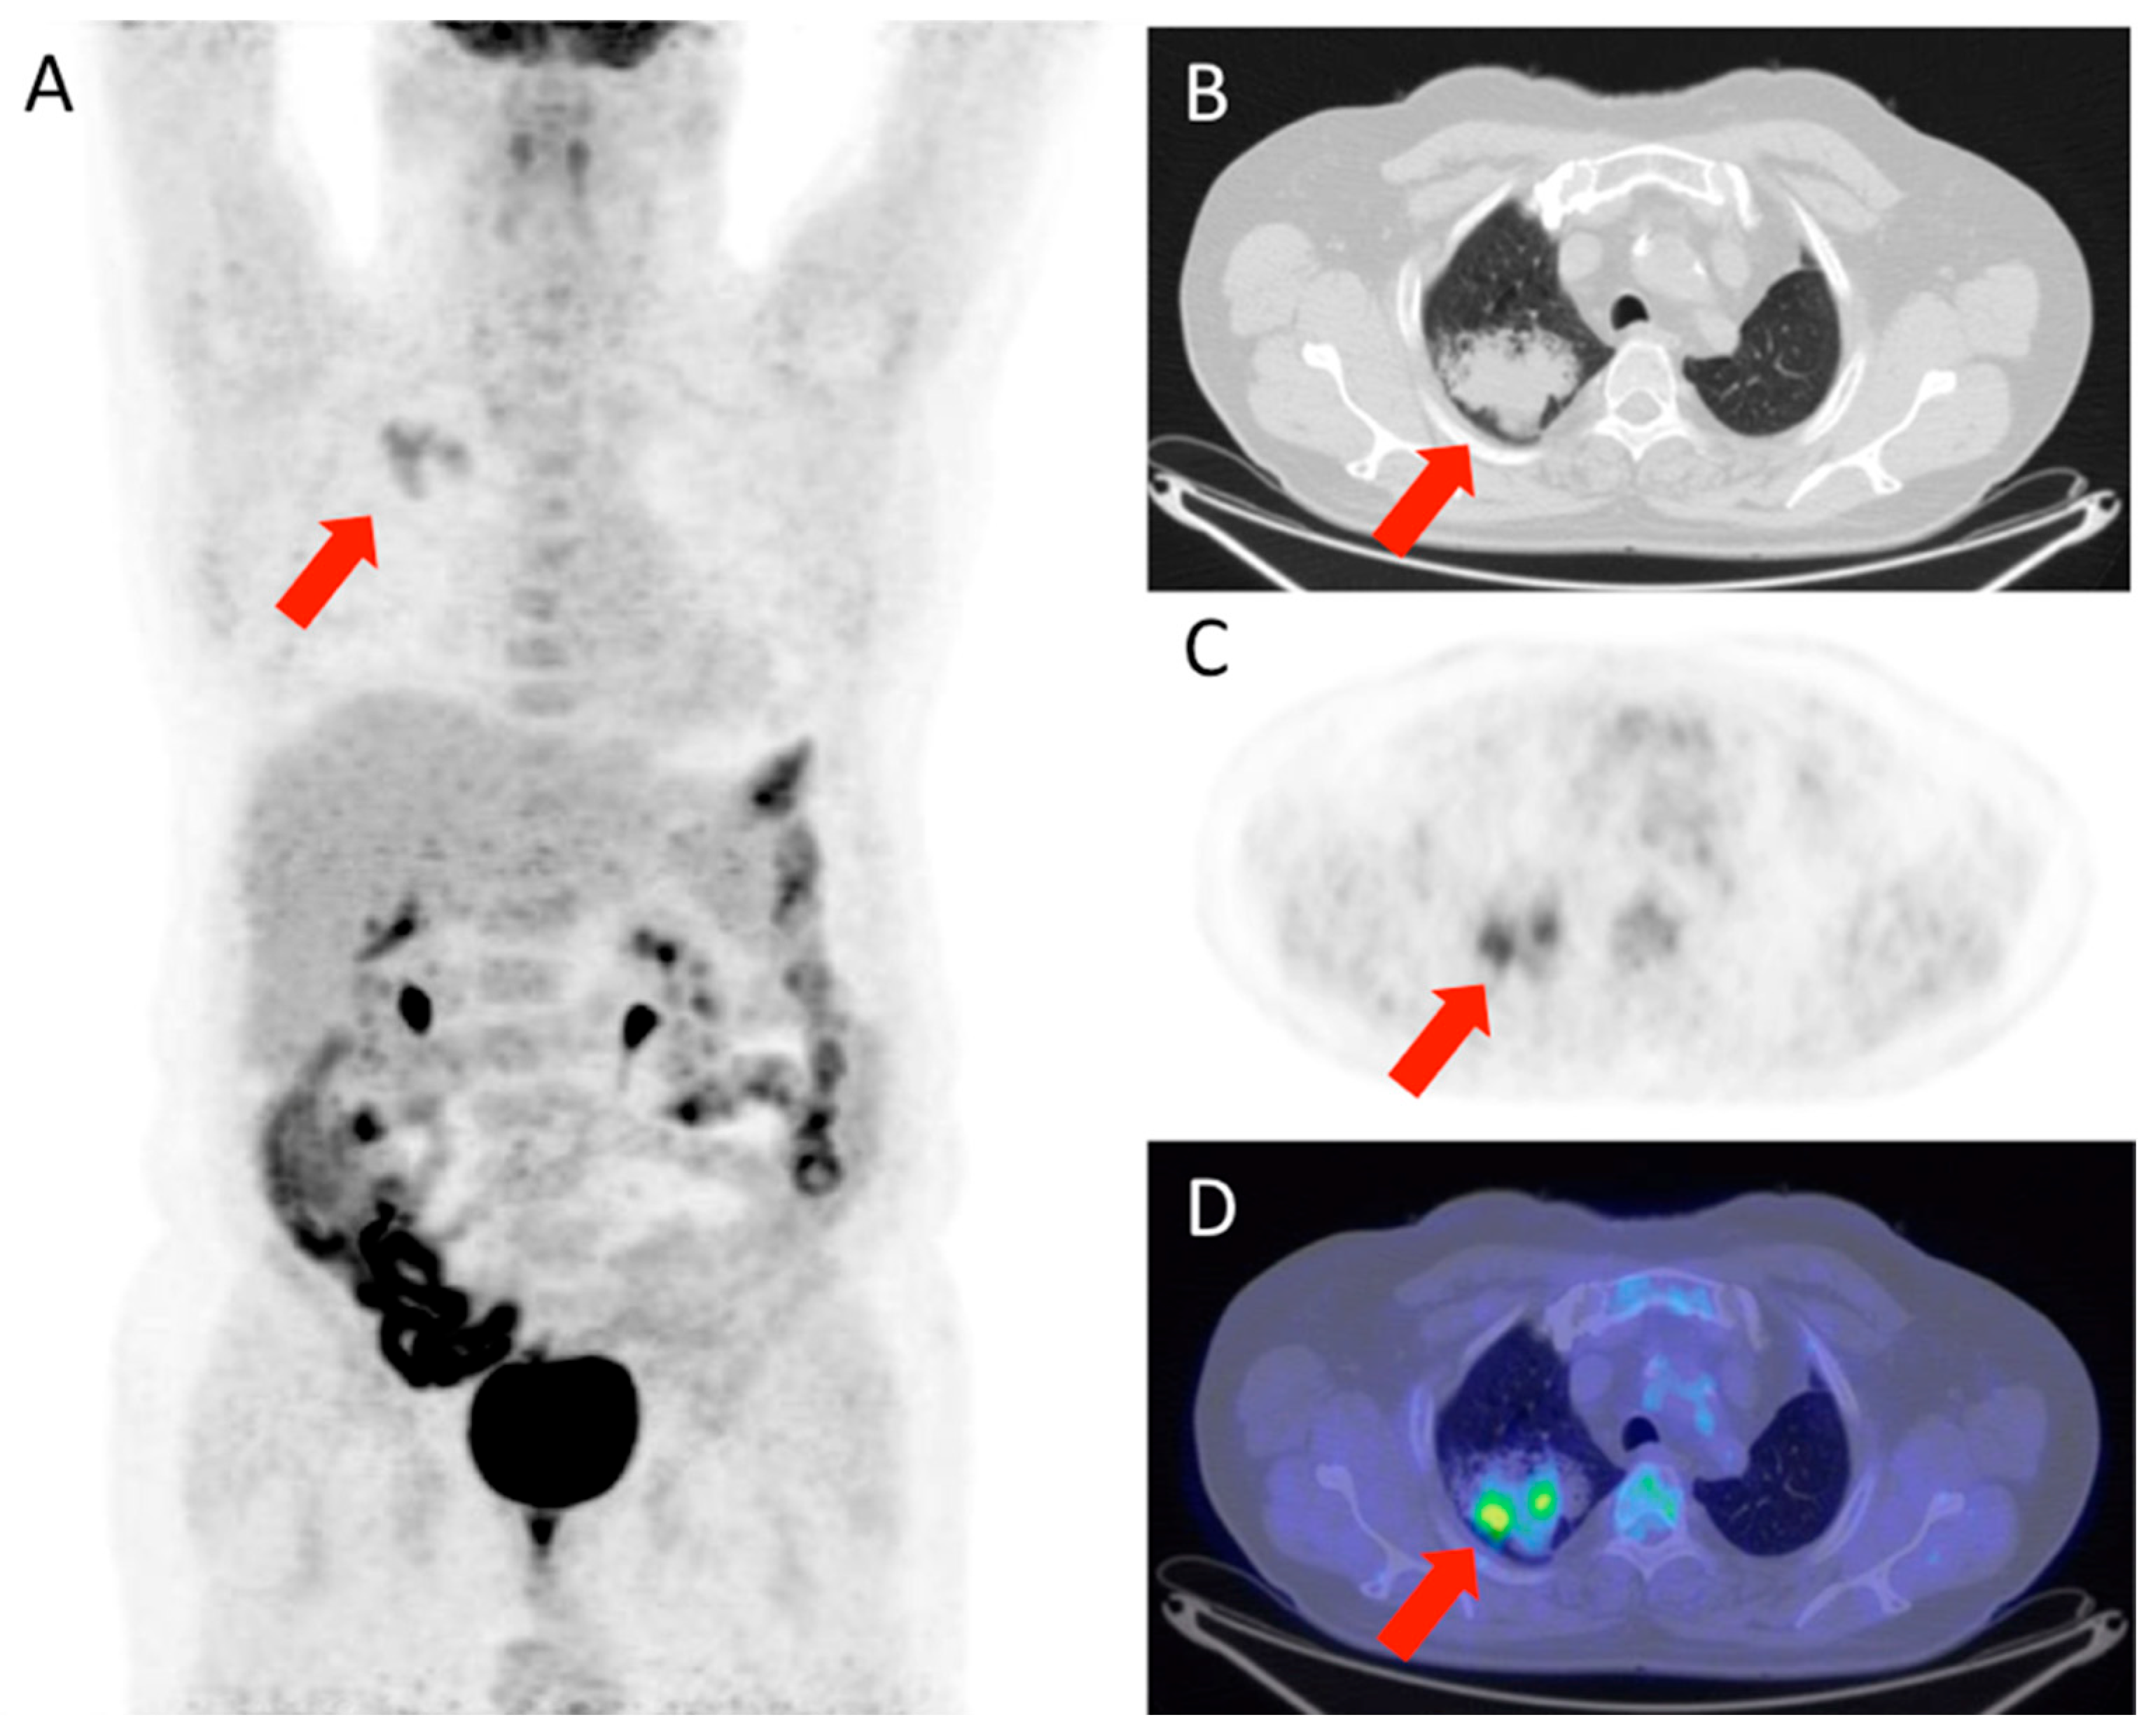

Figure 1 and Figure 2 show, respectively, examples of patients with lung relapse and a patient with phlogistic reaction to EBRT. In detail, Figure 1 shows images of a patient (male, 68 years old) with lung recurrence; PET/CT images with 18F-FDG are shown of a patient diagnosed with right lung adenocarcinoma who underwent surgery two years earlier and subsequently underwent radiotherapy for right lung recurrence, and the contrast-enhanced CT scan (Figure 1B) performed three months after the end of radiotherapy showed extensive pulmonary thickening in the right lung. Figure 2 shows an example of a patient with pulmonary inflammation: it shows the 18F-FDG PET/CT scan of an 82-year-old male patient diagnosed with left lung adenocarcinoma who underwent RT. The chest CT scan performed 6 months after the end of RT showed a lesion in the left lung with spiculated margins and pleural connection streaks. The ^18F-FDG PET/CT was interpreted as positive for ^18F-FDG uptake; MIP images (A), axial and coronal CT (B, C), PET (D, E), and fusion images (F, G) described the uptake of ^18F-FDG as focal, deep, and homogeneous. The semiquantitative parameters were as follows: gSUVmax 2.3, MTV 47.60, pSUVmax 2.1, dSUVmax 1.9, MSD 1.1, and IDSD% 90.5%. The lesion was initially interpreted as a pulmonary recurrence; however, follow-up showed that it was a side effect of EBRT as it resolved within 6 months.

Figure 2. Patient with lung phlogosis. The images shown (AG) are sequences from the same PET/CT of a patient under consideration; specifically, (A) is a total body scan, (B,C) are axial and coronal CT scans of the chest; (D,E) are the corresponding PET scans in axial and coronal views; (F,G) show the fusion of CT and PET to illustrate the station level of the region of interest.